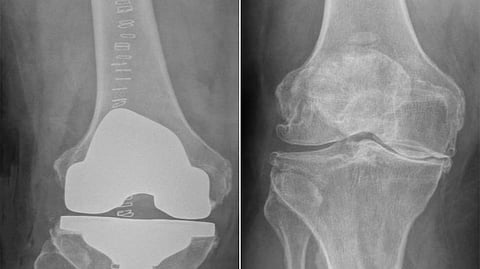

تمكن مستشفى الدكتور سليمان الحبيب بالحمراء، من إجراء عملية نوعية وناجحة، لاستبدال مفصل الركبة، لـ"ستيني" عانى من الخشونة والاحتكاك الحاد وتلف الغضاريف، وغيرها من التبعات الحادة، ذكر ذلك د. نايف بن نويهض الشهراني استشاري جراحة العظام واستبدال المفاصل رئيس الفريق الطبي المعالج.

وقام الفريق الطبي بدراسة الحالة بدقة على ضوء نتائج الفحوصات، بحثاً عن تدخل طبي، وخلص إلى أن هناك إمكانية لإجراء عملية لاستبدال المفصل، وبالفعل أجريت له عملية تم فيها، استبدال مفصل الركبة، باستخدام مفصل صناعي يناسب الحالة، مع الاستعانة بأحدث الأجهزة الطبية، وتكللت العملية ولله الحمد بالنجاح، وتمكن المراجع من المشي بعد العملية مباشرة.

وأوضح د. الشهراني أن الفريق الطبي استخدم تقنية متطورة في إجراء العملية، حيث قام بمحاكاة تشريح الركبة إلى ما قبل الخشونة، وهذا يجنب المراجعين الصعوبات المتمثلة في الآلام الحادة بعد العملية، وأيضاً طول مدتي التنويم والعلاج الطبيعي والتأهيل، والتي كانت تجعل المراجعين يترددون كثيراً قبل اتخاذ قرار الخضوع لعمليات الاستبدال، على الرغم من أن أعراض "الاحتكاك والخشونة" تحول حياة المصابين إلى معاناة دائمة، بسبب الآلام المستمرة، وعدم القدرة على الحركة والنوم وممارسة الحياة بشكل طبيعي، مشيراً إلى أن المراجع تم تدريبه على كيفية السير على قدميه قبل العملية.